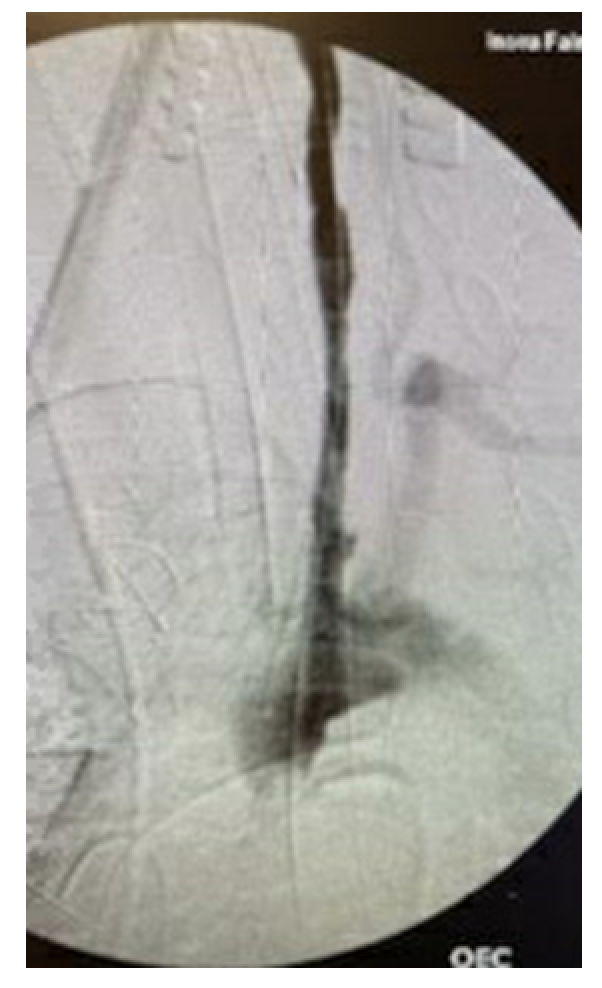

Postoperatively, the patient was noted to have left-sided weakness and a markedly decreased level of consciousness (LOC). There was no evidence of stroke or intracranial hemorrhage on head computed tomography (CT). A head and neck CT angiogram demonstrated near total effacement of the true lumen of the left CCA (Figure 1) and 60% stenosis of the mid-right CCA from a dissection flap involving the vessels (Figure 2).

The following day, the patient underwent retrograde stenting of the left CCA by cut down over the carotid bifurcation. A 10-mm x 80-mm followed by a 12-mm x 100-mm from distal to proximal Abre self-expanding venous stent was utilized for the repair. We were able to restore the true lumen of the left CCA (Figure 3 and Figure 4).